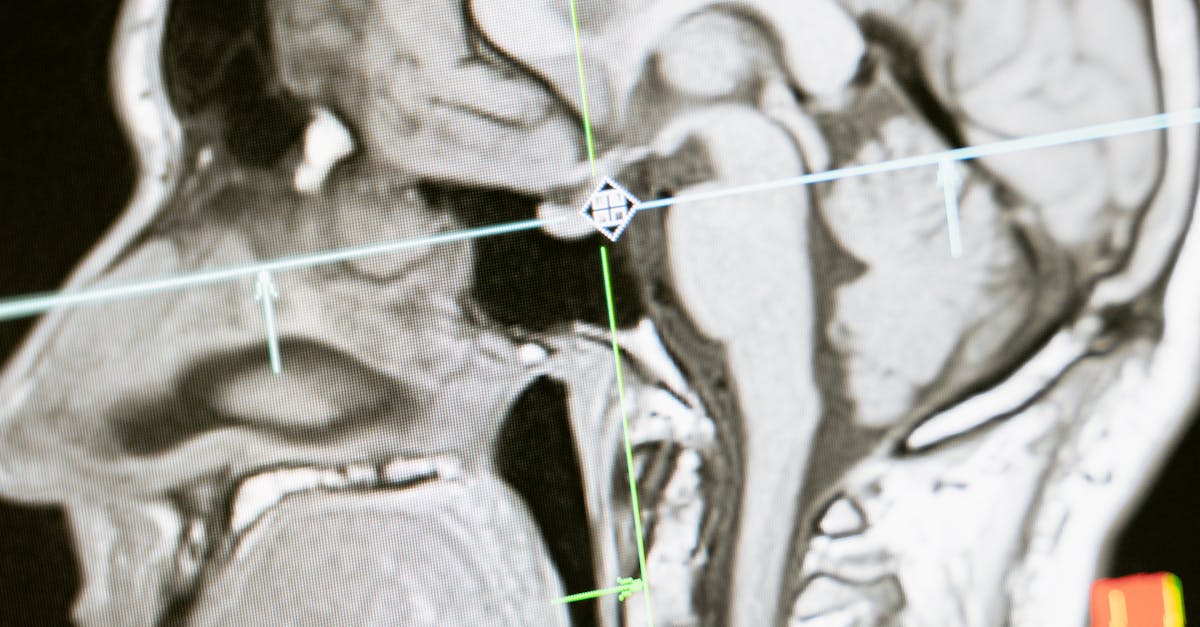

While people did the tasks, they lay in an fMRI machine. This tool tracks blood flow in the brain. Active areas get more oxygen-rich blood. The machine makes 3D maps of that flow. It shows exactly which spots light up during thinking or remembering.

fMRI gives clear pictures without harm. It spots changes as small as blood flow shifts. In this case, it captured moments of successful recall. Both memory types fired up the same hubs. These include areas in the middle of the brain that link ideas and experiences.